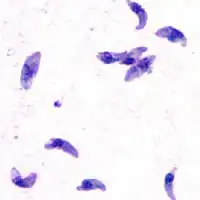

Toxoplasma gondii tachyzoïet

Aseksuele ontwikkeling van de parasiet kan in elk type cel van de tussengastheer plaatsvinden (de mens, maar ook een grote variëteit aan dieren), behalve in de rode bloedcellen. Het actieve stadium van de parasiet is de tachyzoïet. Deze komt na het inslikken vrij uit de oöcyste of uit de weefselcyste, dringt de gastheercel binnen en deelt intracellulair. Het delingsproces gaat door tot de gastheercel barst. De vrijgekomen tachyzoïeten dringen direct weer nieuwe cellen binnen en beginnen opnieuw met delen. Door een nog niet geheel begrepen mechanisme ontstaat na enige tijd een omslag in dit proces en ontstaan weefselcysten. Deze bevatten bradyzoïeten, dat wil zeggen een veel trager stadium van de parasiet met een zeer laag stofwisselingsniveau en slechts weinig deling. De bradyzoïet bevindt zich in de intracellulaire weefselcyst met een diameter van ongeveer 100 μm en bevat enkele duizenden parasieten. De weefselcysten variëren in grootte (tot 200 μm) en bevatten wisselende aantallen parasieten, variërend van enkele tot 3000 bradyzoïeten.

Tachyzoïten -

Twee tachyzoïten omgeven door een membraan -